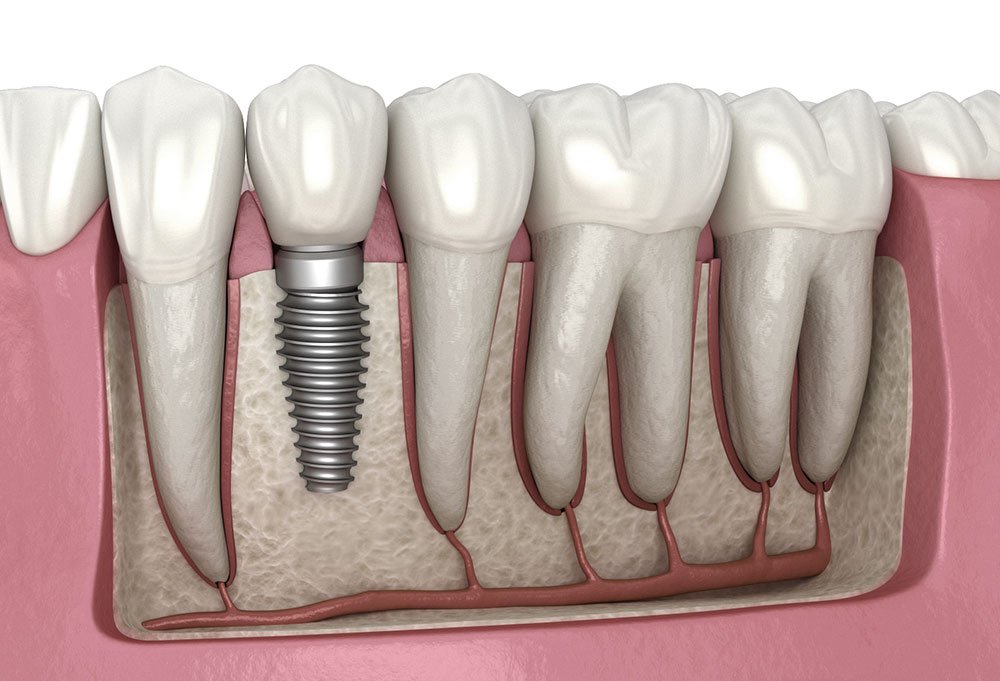

Dental implants are a modern and long-lasting solution for replacing missing teeth. They consist of a small titanium post that is surgically placed into the jawbone, acting as an artificial tooth root.

Once the implant has integrated with the bone, a custom-made crown, bridge, or denture is attached on top, restoring both the appearance and function of the missing tooth.

Preserves jawbone

Prevents bone loss that occurs after tooth extraction

No damage to neighbouring teeth

Unlike bridges, implants do not rely on adjacent teeth for support